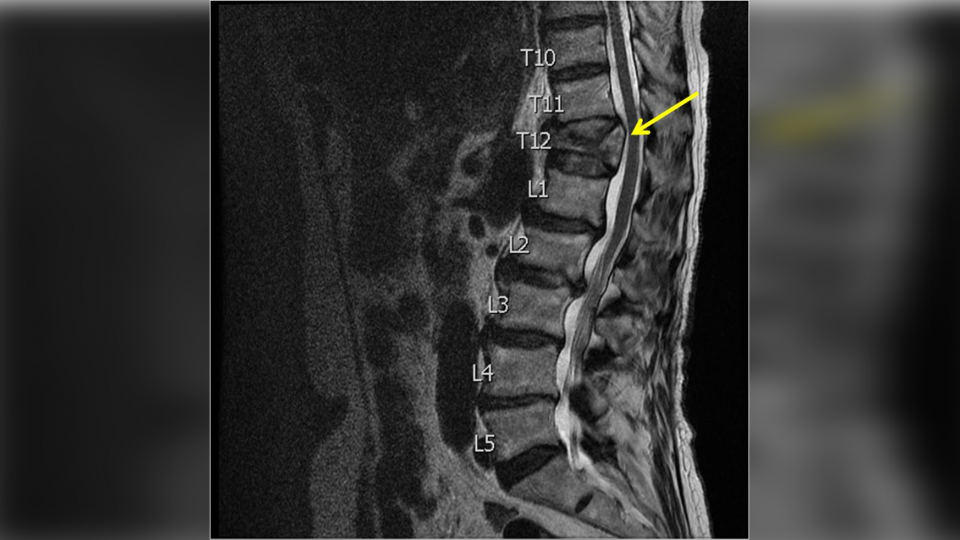

▲女病患脊椎因為舉重滿是傷痕(示意圖/翻攝自柯紹華臉書

桃園敏盛醫院神經外科主任柯紹華在臉書PO文表示,曾經有位因為長期背痛的女病患向他就診,一照X光卻嚇傻了,女病患的脊椎滿是陳年舊傷與不同程度的壓迫性骨折,他驚訝的和對方說:「光看這影像就知道妳一定很痛厚...」,女病患只是點了點頭,他又接著問:「可是妳這麼年輕脊椎就這麼多問題,過去是一直從事粗重的勞動工作嗎」,對方這才靦腆回應「喔,我從前是舉重國手,現在在工廠搬貨...」。